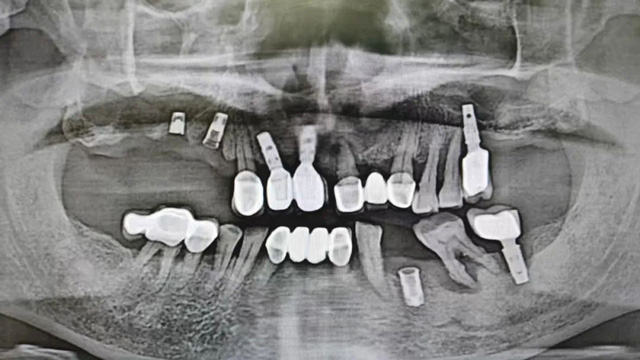

经过检查,余国庆医生发现吴叔叔的口腔情况比较复杂。检查报告显示,他口腔里现存完整的种植牙只有两颗,上下颌各1颗。

“上面种了4颗,断了两颗,脱落1颗,只有1颗能用,下面有一颗牙冠脱落,另一颗有种植体周围炎,有明显的骨吸收。”吴叔叔剩下的天然牙也不好,做了几处修复,之前的牙冠修复用的都是烤瓷牙,有好几颗磨损严重露出了金属。由于存在缺牙、不良修复体等情况,口腔整体咬合紊乱,进食很困难。

治疗前口腔全景片